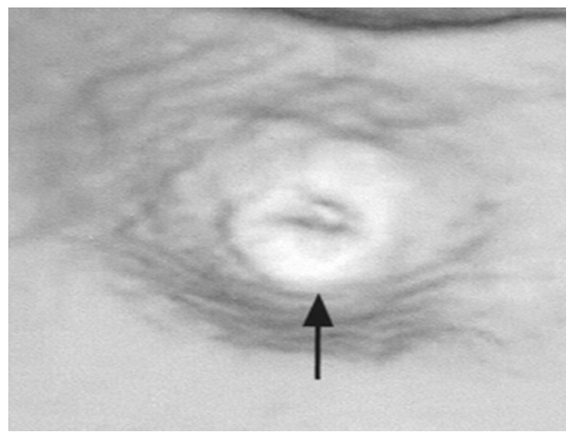

On routine investigation hemoglobin 7.8 g/dL, leukocyte count 20.6x103/µL, MCV 90 fL, MCH 30 pg, and platelet count was 60.0x103/µL. General blood picture revealed 22% blast cells with auer rods. Liver function tests and coagulation profile were normal. Serum creatinine was 1.2 mg/dL and blood urea was 24 mg/dL. Mid stream urine examination showed protein in traces, 2–4 pus cells/high power field, and numerous red blood cells along with amorphous deposit of crystals. Urine culture and sensitivity were sterile, there was no evidence of glomerulonephritis. FDP and D-dimer were normal. Patient refused PCR test for detection of viral etiology. Ultrasonography of kidney and computed tomography (CT) scan of abdomen revealed no abnormality of urinary tract region. Cystoscopic examination of the bladder was normal. (Figure 1) The bone marrow aspirate and cytochemistry were consistent with the diagnosis of acute myeloid leukemia of M4FAB subtype. The patient was kept on induction chemotherapy (daunorubicin 50 mg/m2/day on day 1, 2, 3 and cytarabine 150 mg/m2/day, intravenous infusion for seven days) and achieved remission. Hematuria subsided within three days after treatment.

Figure 1: Cystoscopy of urinary bladder of patient showing normal healthy wall and ureteric orifices.

Hematuria as the only or main presenting feature in acute leukemia is rare and to best of our knowledge only 17 cases have been reported till now. [5] [6] In this case blood investigation reports were suggestive of acute leukemia. Although any organ system in the body can be infiltrated by leukemic cells but involvement of renal system is unusual. If the urinary tract is infiltrated by leukemic cells, kidney is the most common site of involvement. [5] [7] Leukemic infiltration of the urinary bladder is very rare, till date only few cases have been reported. [5] [6] [7] [8] In this case though cystoscopy was normal but it could not ruled out occult leukemic infiltration, this could be confirmed only by biopsy but patient refused for the same.